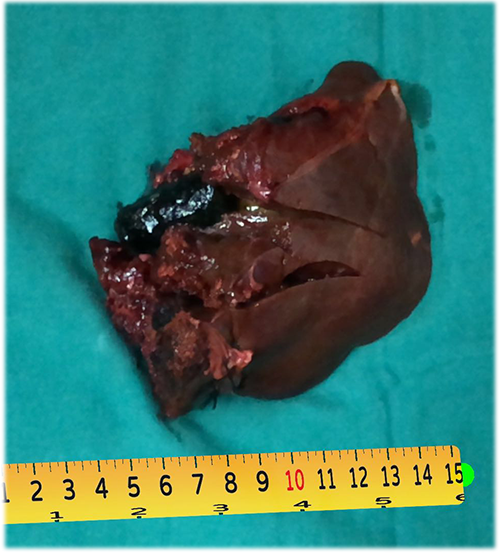

左肝管结石--左肝叶切除